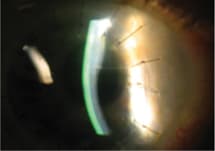

The cornea is the most commonly transplanted solid tissue, with more than one million corneal transplants performed in the United States since the 1960s (Eye Bank Association of America, 2009; Kaufman et al, 1998; Sellami et al, 2007). The most common indications for corneal transplant include corneal dystrophy, aphakic bullous keratopathy, and keratoconus (Rao, 1991). Full thickness (Figure 1) or lamellar grafts are able to restore vision or integrity to a cornea that has been irreversibly compromised by disease or trauma when all other medical management options have failed.

Figure 1. Corneal graft with uninterrupted sutures.